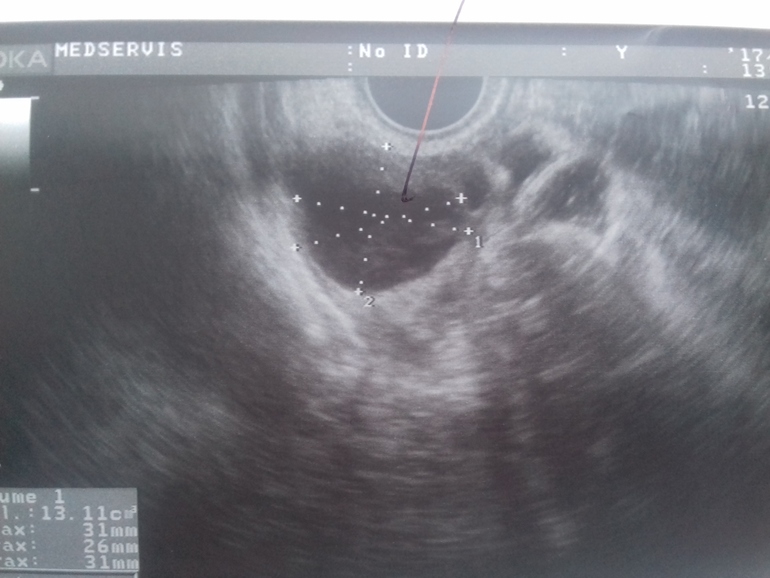

Как отличить кисту ЖТ от фолликулярной?

Какая это киста?

Вам уже верно написали, что определить можно по наличию/отсутствию кровотока. Но к сожалению, не все узисты это смотрят... И пишут потом прост киста, не уточняя какая. По фото можно предположить только, да и то сомнительно. Обычно фолликулярная киста прям темная, почти черная, киста жт - серая с неровными краями. Но это субъективно все.

На фото явно киста желтого тела, она имеет характерное строение, структуры ( ячеистая), фолликулярная киста такой не бывает.

Мне врач несколько раз показывала кисту жт, она всегда как будто сеточкой была, но по фото это нельзя определить, нужно ещё жидкость смотреть и кровоток